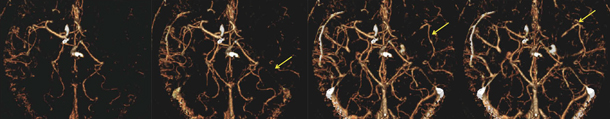

CTPのデータから,4D CTAを再構成することができる。CTAで左中大脳動脈の末梢が描出されていたのは,血流が逆行しているためであることがわかった(図4)。ある程度血流が保たれていると判断し,緊急バイパス術は不要と診断した。CTP,4D CTAが治療方針の決定に有用だった症例である。

図4 症例2:4D CTAによる脳血流動態評価

側副血行路を介した逆行性の血流が認められる(←)。